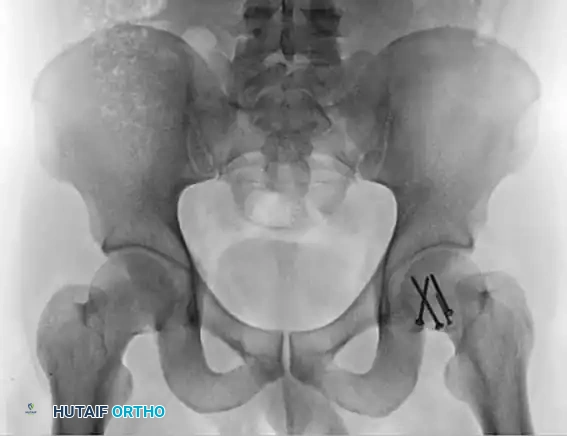

Pre-Reduction Radiographic Assessment

Standard Advanced Trauma Life Support (ATLS) protocols dictate an anteroposterior (AP) radiograph of the pelvis. This single view is usually sufficient to diagnose a posterior dislocation and identify gross concomitant fractures of the femoral head, neck, or acetabulum.

FIGURE 55-52 C: Preoperative AP radiograph demonstrating a posterior hip dislocation with a concomitant femoral head fracture.